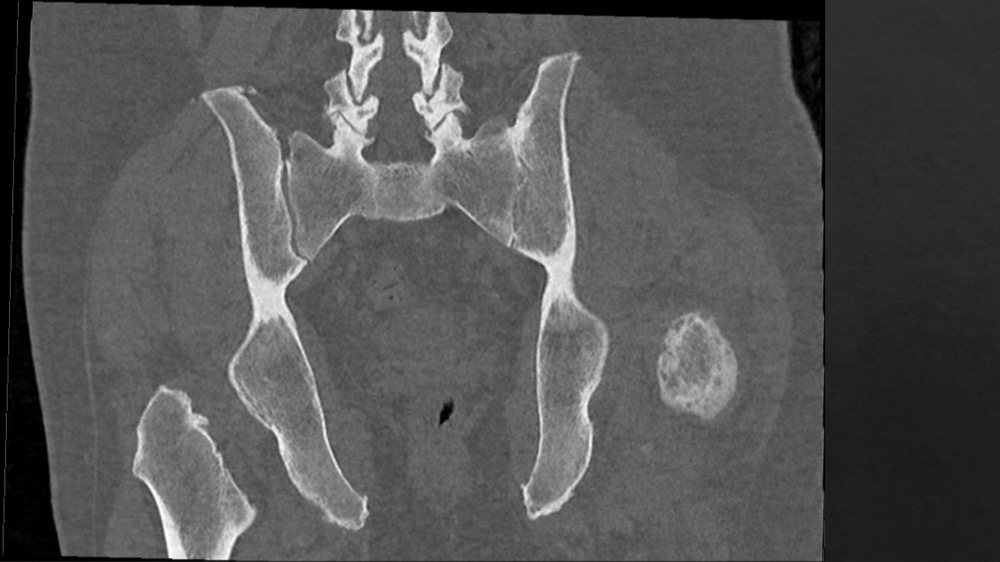

Bone Club

Aida Ksouri 22/06/2020